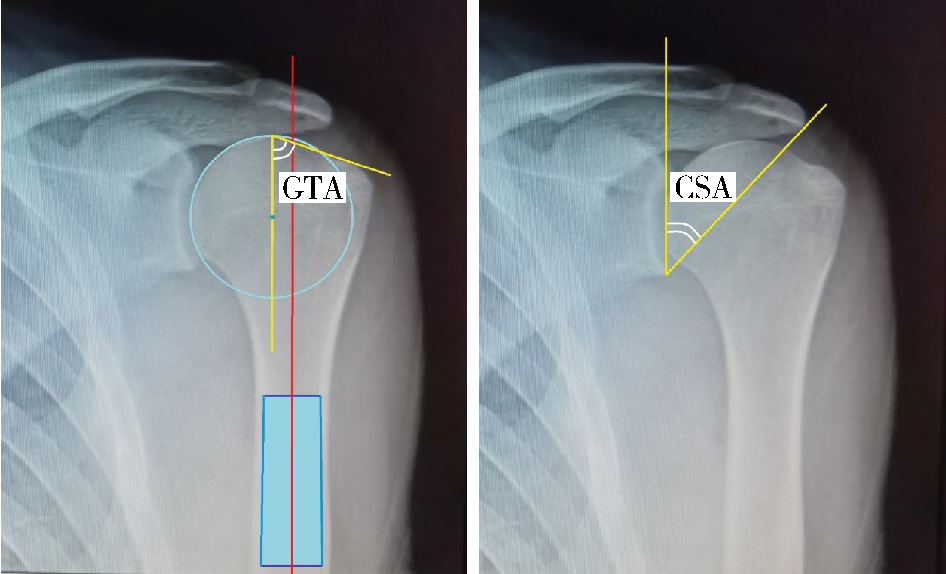

Figure 2

Measurement methods of GTA and CSA on apraxis of scapula Greater tuberosity angle (GTA) is made by two crossing lines. The first line passes through the center of humeral head and parallels to the humerus diaphysis, and the second one connects the upper border of the humeral head to the most superolateral edge of the greater tuberosity. Critical shoulder angle (CSA) consists of the angle with two crossing lines. One of which was drawn from the glenoid superior to inferior border, the other was drawn from the glenoid inferior border to lateral aspect of the acromion."